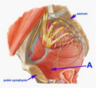

Label A-D

A

A: Perineal branches of pudendal nerve

B: Levator ani muscle

C: Inferior rectal nerves

D: Gluteus maximus muscle